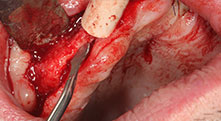

Würden Sie uns kurz beschreiben, wie Sie zum Beispiel beim Mobilisieren von Knochenblöcken für Transplantationen vorgehen?

Bratu: Wir bevorzugen Knochenentnahmen von der Linea obliqua externa des posterioren Unterkiefers, nicht aus der interforaminalen Region. Nach der Weichgewebsinzision verwenden wir die neuen Sägen, um den Umfang der Knochenentnahme zu definieren. Wir erledigen damit in fast 80 Prozent der Fälle auch die gesamte Präparation. Zusätzlich verwenden wir eventuell andere Piezo-Instrumente und zuletzt einen Meißel, um den Block zu mobilisieren. Das ist für uns eine sehr effektive Operationstechnik.

Bratu: Wir augmentieren im seitlichen Unterkiefer gern mit der Sandwich-Technik. Dabei wird ein Knochendeckel mit der Piezosäge präpariert und das krestale Fragment mit Mikroschrauben fixiert. Dazwischen platzieren wir eine Mischung aus autologem Knochen und xenogenem Knochenersatzmaterial. Das funktioniert sehr zuverlässig. Bei Kieferkammspaltungen im Unterkiefer sollten Sie nie auf ausreichend dimensionierte vertikale Schnitte verzichten. Sonst kann der Knochen leicht frakturieren.